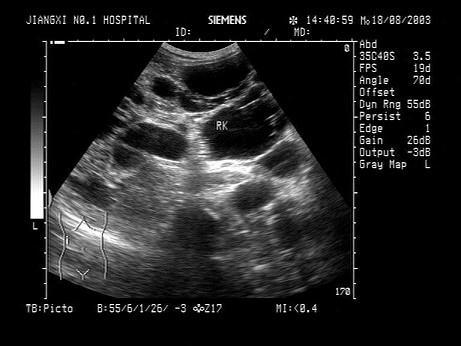

问题 男,有高血压病史,腰部触及包块,超声检查如图所示,最可能的诊断是?(?)

选项 A.肾重度积水 B.多发性肾囊肿 C.多囊肾 D.肾多囊性发育异常 E.肾脓肿

答案 C